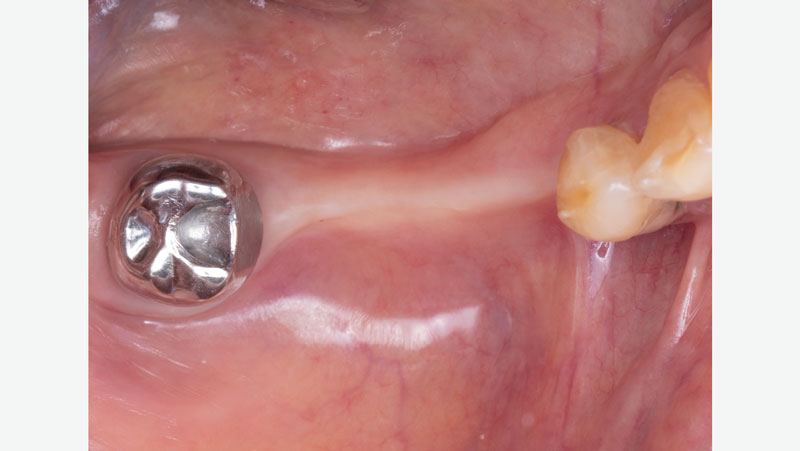

For existing partials, examine the occluding tooth contact, the position of the tongue, how the retentive and reciprocal arms are placed, and how it rests on the occlusal surface of the crown. Be sure to also examine the patient’s oral environment when the partial is removed, noting the spacing and the gingival region around the crown.

Original-crown-without-partial

Original crown without partial

Ridge-spacing-without-partial

Ridge spacing without partial